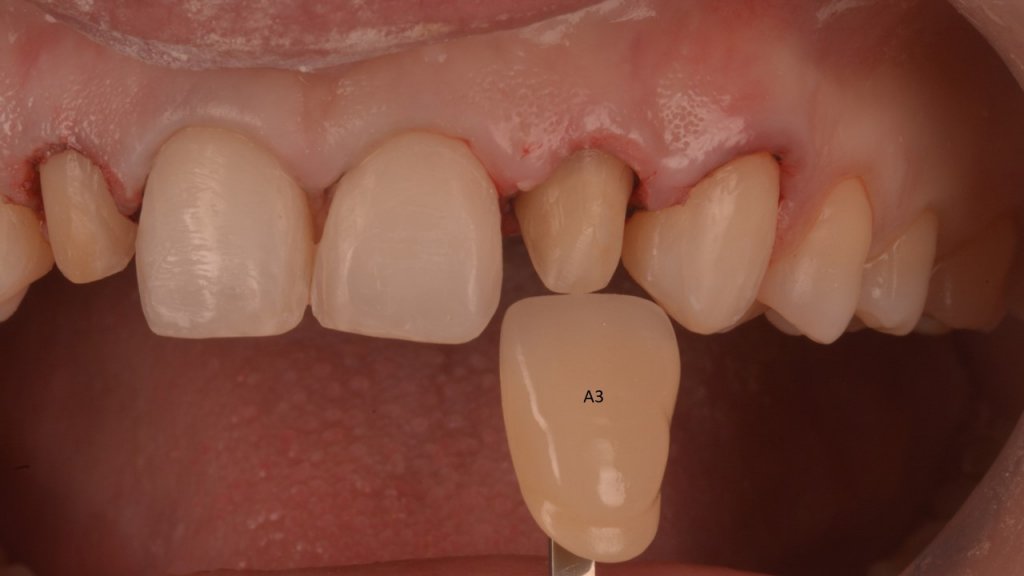

Me cuenta que ya en pasado, a los 18 años, se sometió a una ortodoncia y intentar enmascarar la microdoncia de los laterales con unas «carillas cerámicas». Esto era el resultado de dicho tratamiento:

Y vamos de Azul (NIC TONE) sin linea de terminación, sufrimos el doble..no tenemos donde agarrar el Clamp y sobre todo donde realmente termina la carilla…

Voy siempre de 2 en 2, claramente cemento antes las Coronas, que me ayudaran a «clampar» y luego las carillas. Pero normalmente empiezo con los laterales que están en el medio y suelen robar el espacio a los otros